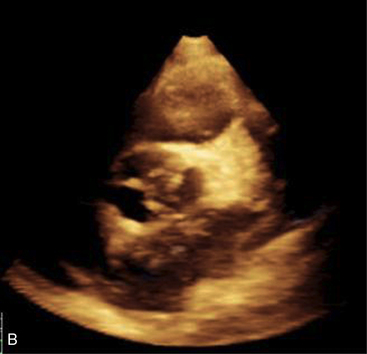

The initial evaluation of a child with suspected myocarditis includes evaluation of the chest radiograph, electrocardiogram (ECG), and cardiac biomarkers. An echocardiogram should be performed to evaluate ventricular function and the degree of any mitral regurgitation.870

The echocardiogram is required to rule out the presence of structural heart disease, and it will enable evaluation of heart size, ventricular contractility, and atrioventricular (AV) valve function. The echocardiogram also will confirm the presence of any significant pericardial effusion.

The echocardiogram demonstrates ventricular dilation, disproportionate ventricular septal thickening, or possible obstruction of the left and/or right ventricular outflow tracts. Echocardiographic findings show globally decreased contractility without regional wall motion abnormalities. Color and pulse-wave Doppler can determine the presence and degree of valve regurgitation, assess cardiac output by aortic flow velocities, determine the degree of diastolic dysfunction by atrioventricular (AV) valve inflow pattern, and estimate pulmonary artery and right ventricular pressures. Echocardiography is beneficial for monitoring patients longitudinally as well as for detecting changes in ventricular function, thrombus formation, wall stress, pulmonary vascular disease, and valvular regurgitation.212